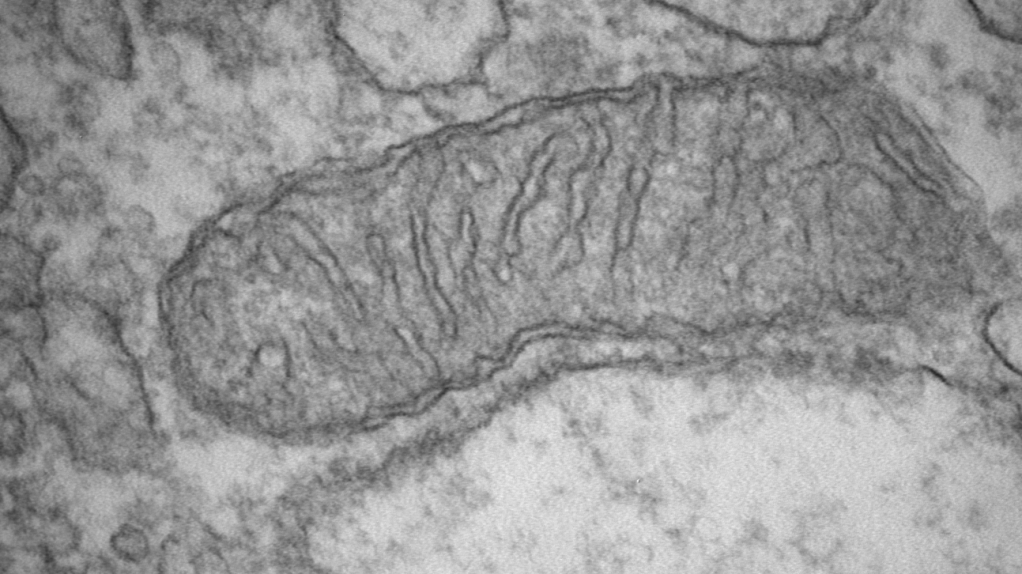

Our laboratory uses genetically engineered mouse models (GEMMs), patient-derived organoid systems, and base editing tools to study of the complex genetic, mitochondrial, and metabolic factors that contribute to prostate cancer pathophysiology and disparities.